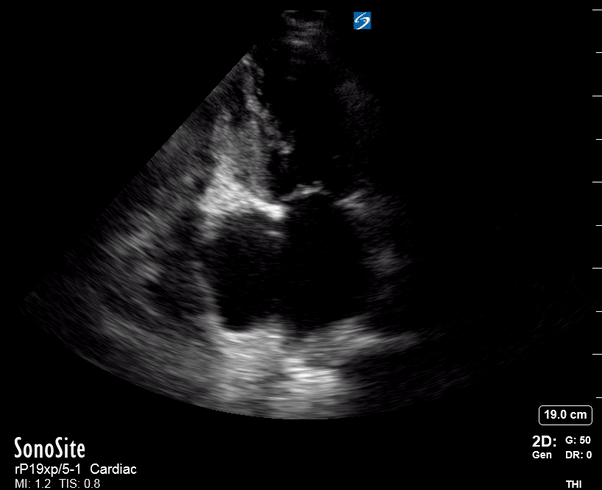

THE VIEWS

The PLAX view is versatile and allows the recognition of multiple landmarks, making it good for visual estimation of LV contractility. It is essential to optimize the view ensuring a true sagittal long axis, as being oblique to the LV chamber may underestimate its size and overestimate its emptying. The PSAX view at the level of the papillary muscles reveals the entire muscular circumference and concentric squeeze of the LV. It is useful to estimate both global function and focal wall motion abnormalities. The A4C view, although technically challenging, provides good insight into the global myocardial function and chamber size.

LV CONTRACTILITY

Qualitative assessment of the LV and visual estimation of Ejection Fraction is based on three parameters:

Endocardial excursion.

Myocardial thickening.

Movement of the anterior leaflet of the mitral valve.

A qualitative assessment is typically categorised as:

Normal (LVEF 50-65%)

Moderately Depressed (LVEF 30-50%)

Severely Depressed (LVEF < 30%)

Hyperdynamic (LVEF > 65%)

SIGNIFICANTLY IMPAIRED / DILATED LV

A severely depressed LV contractility, particularly when paired with a plethoric IVC or lung B-lines, indicates systolic heart failure. Chronically raised afterload can lead to severe dilation of the LV.